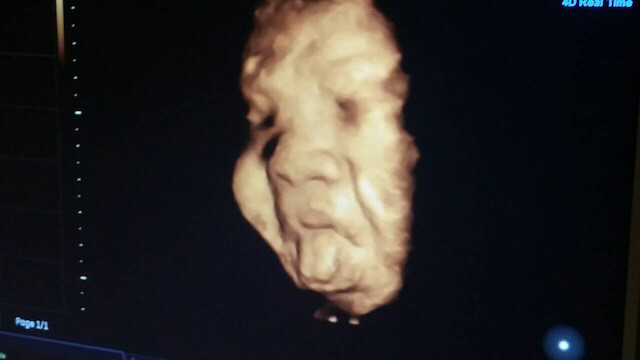

ナイス表情賞

受賞者:ココちゃんママ さん

エコー写真撮影時のエピソード(妊娠37週目:37w5d)

いつも通りにエコーをしていたらなんとあっかんべーをしていました!いつもは笑ったりすることのない診察室に私と主人、お医者さんの笑い声が溢れました。見た瞬間、みんなは驚きとともに大爆笑でした!お医者さんにとっても珍しかったようで顔だけアップにしてじっくり見ていました。

編集部のコメント

なんといってもインパクトのある表情!そして、ママやパパだけでなくお医者さんをも大爆笑させるその姿に編集部一同心を射抜かれました!

お子さんは女の子とのこと。チャーミングな女の子になりそうですね!将来が楽しみです!